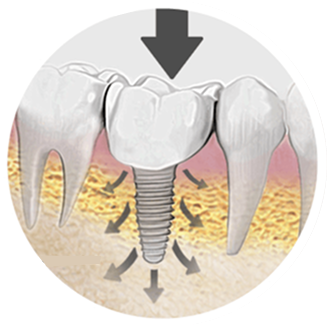

Implant Placement using surgical guides for precision, the titanium implant is placed into your jawbone, typically 30-60 minutes with local anaesthesia.

A 3-6 month healing period for implant to integrate with bone (osseointegration). You’ll have a temporary solution during this time.

Dental implants provide superior stability and function because they are anchored into the jawbone, preventing slipping and discomfort common with dentures. They help preserve jawbone density, maintain facial structure, and do not require adhesives.